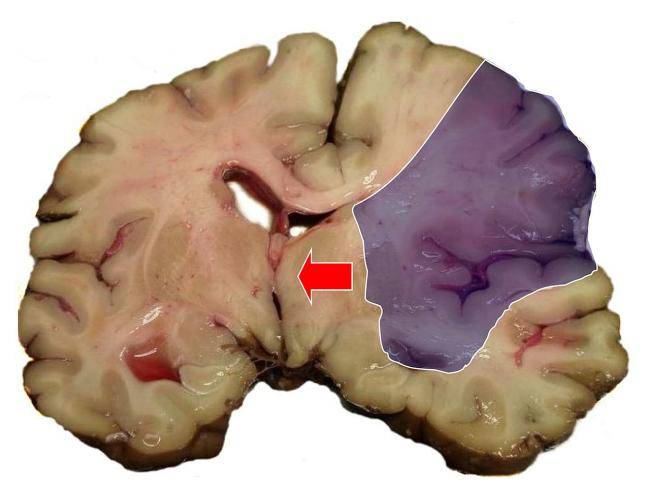

İnsult – beyin qan dövranının kəskin pozulması nəticəsində baş beyində ocaqlı zədələnmənin yaranması ilə xarakterizə olunur. İşemik və ya hemorragik xarakter daşıya bilər. İnsult əksər hallarda bədənin sağ və ya sol yarısında ətraflarda qəfil zəiflik, üzün asimmetriyası, huşun, nitq və görmənin pozulması, başgicəllənmə ilə təzahür edir. Diaqnoz klinik, laborator, tomoqrafik və damar müayinələrinin nəticələri əsasında qoyulur. Müalicə orqanizmin həyat fəaliyyətinin təminindən, ürək, tənəffüs və metabolik pozğunluqların korreksiyasından, serebral ödemlə mübarizədən, spesifik patogenetik, neyroprotektor və simptomatik terapiyadan, ağırlaşmaların qarşısının alınmasından ibarətdir.

İşemik insult: Bu qan təchizatının çatışmazlığı nəticəsində beynin ocaqlı (fokal) zədələnməsindən əmələ gələn insult növüdür. Bu sindrom 24 saatdan çox çəkən və ya bir sutka ərzində ölümə gətirib çıxaran nevrolojı simptomların kəskin inkişafı ilə xarakterizə olunur. Kəskin serebral işemiya nəticəsində yaranan ocaqlı nevroloji defisit və ya retinal işemiya nəticəsində yaranan görmənin monokulyar pisləşməsi (amaurosis fugax) 24 saat ərzində tam keçib gedirsə, bu sindrom tranzitor işemik həmlə (TİH) kimi təsnifata daxil edilir. Onu demək olar ki, insultların 85%-i işemik insultlardır.

Qanaxma tipli insult: Bu növ beyindəki qan damarından beyinə qan sızdıqda meydana gəlir . Xəstəliyin rast gəlinmə faizi işemik insultdan daha azdır. Ancaq buna baxmayaraq insult nəticəsində ölümlərin 30%-i bu növdən qaynaqlanır.